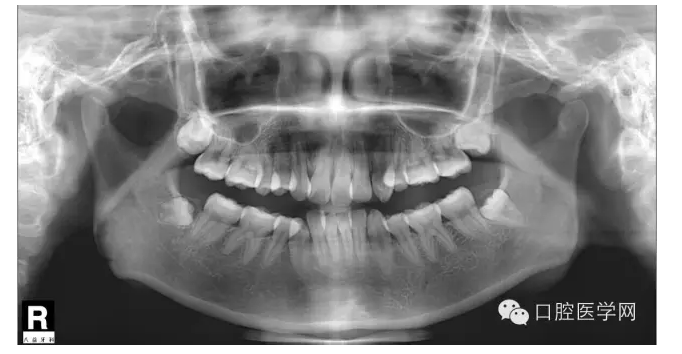

這是一位我同事接診的一位患者,成年女性,安氏II類,高角,下頜后縮,重度深覆合,上下中線右偏,原本做過(guò)一次矯正,4個(gè)4已經(jīng)拔除。

我同事又給她拔了左邊兩個(gè)5,然后我同事離職了,把患者扔給我。

所以這個(gè)患者我選擇使用弓絲壓低下前牙。但由于雙尖牙只剩下15,45,所以我們將37,47,納入矯正。